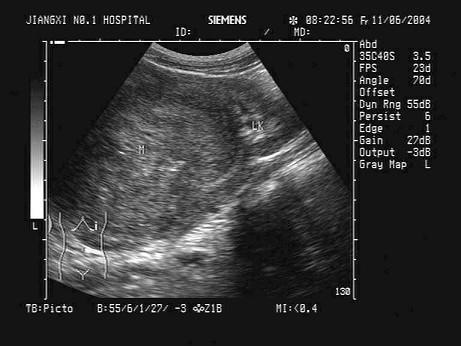

问题 男性,4岁,因左肾区不适就诊,无外伤史,无发热,左腹部可扪及肿块。根据其声像图,可能的诊断为?(?)

选项 A.肾母细胞癌 B.急性肾炎 C.肾血管平滑肌脂肪瘤 D.肾脓肿 E.肾癌

答案 A